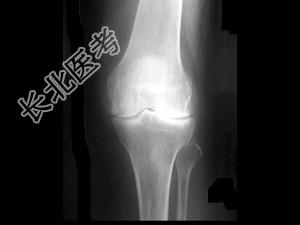

- 单项选择题女,50岁, 手指关节肿痛,晨僵, 结合图像,最可能诊断是 ( )

A、关节结核

B、牛皮癣性关节炎

C、痛风性关节炎

D、类风湿关节炎

E、Reiter综合征